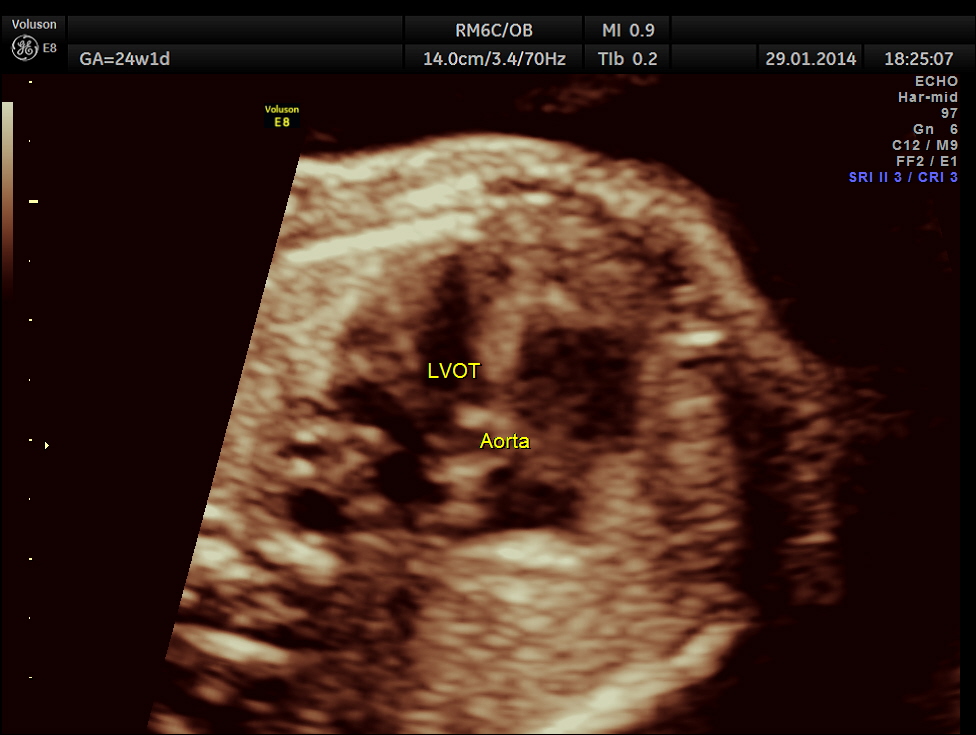

Images of the other organs are given below.